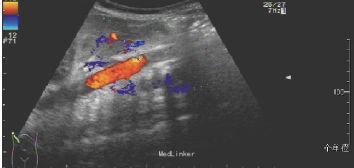

T 37.2℃,P 126次/min,R 62次/min,BP 88/56mmHg。神清,皮肤黏膜无出血点、瘀斑,前囟平软,1.5cm×1.5cm,呼吸稍促,三凹征阴性,双肺呼吸音粗,闻及少许痰鸣音,心前区无隆起,心率 126次/min,心前区闻及Ⅱ/6级收缩期杂音。下肢肢端稍凉,CRT<2s。心脏彩超:卵圆孔未闭。腹主动脉超声:腹主动脉近肾动脉水平内可见实质性低回声充填,内未见明显血流信号,双侧髂外动脉血流速度约15cm/s,呈阻塞性频谱。腹部增强CT示:左肾动脉平面以下腹主动脉、髂总动脉未见显影,考虑为动脉栓塞可能。

新生儿动脉血栓非常少见,动脉栓塞的临床表现有肢端苍白、青紫、发凉、坏疽、动脉搏动消失、肾衰、充血性心衰和高血压等,血管超声是确诊的首选方法,同时也是监测疗效的主要手段。